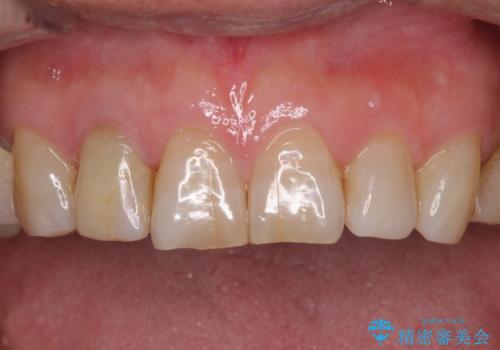

憧れの白い歯に 全顎セラミック治療

- 60歳を越え、黄ばんだ前歯をセラミッククラウンできれいな口元にしたいとのことで来院された患者様です。

健全な歯を削ってセラミッククラウンに置き換えることは、本来避けるべき治療と考えますが、今回は①患者様が60歳を越えていること、②要改善の咬合により抜歯が必要な奥歯があること、③反対咬合の前歯改善の手段としてセラミック治療が選択肢にあることなどから、全顎的なセラミック治療を行うこととしました。